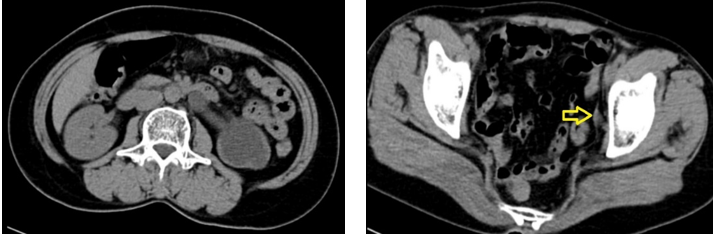

Vừa qua khoa Ngoại tổng hợp, Bệnh viện Đa khoa tỉnh Quảng Trị đã thực hiện thành công phẫu thuật nội soi ổ bụng cắm lại niệu quản cho một bệnh nhân nữ 55 tuổi. bệnh nhân này có tiền sử nội khoa bình thường, 3 năm trước được phẫu thuật cắt tử cung toàn phần đường bụng. gần đây thấy đau tức vùng hông trái, đi siêu âm phát hiện thận trái ứ nước độ 4 nên nhập viện. Thăm khám lúc vào viện thấy bệnh nhân đau tức vùng hông trái, thận trái không lớn , siêu âm thấy thận trái ứ nước độ 4 nhu mô thận mỏng, không thấy thấy sỏi cản quang niệu quản. Trên phim chụp hệ niệu không chuẩn bị không phát hiện sỏi cản quang hệ tiết niệu. Bệnh nhân sau đó được chụp niệu đồ tĩnh mạch thấy chức năng thận trái giảm mạnh. Do chưa tìm thấy nguyên nhân ứ nước, bệnh nhân được chỉ định chụp cắt lớp vi tính không thuốc (CT Scan), trên hình ảnh thấy thận trái không lớn, ứ nước độ IV, nhu mô thận mỏng, niệu quản giãn 9-10mm từ đoạn bụng đến đoạn chậu, rất hẹp ở đoạn tiểu khung, chẩn đoán cuối cùng là thận trái ứ nước độ IV do hẹp niệu quản đoạn tiểu khung.

Hình 1 : Thận trái ứ nước độ 4 và vị trí niệu quản hẹp (mũi tên vàng)